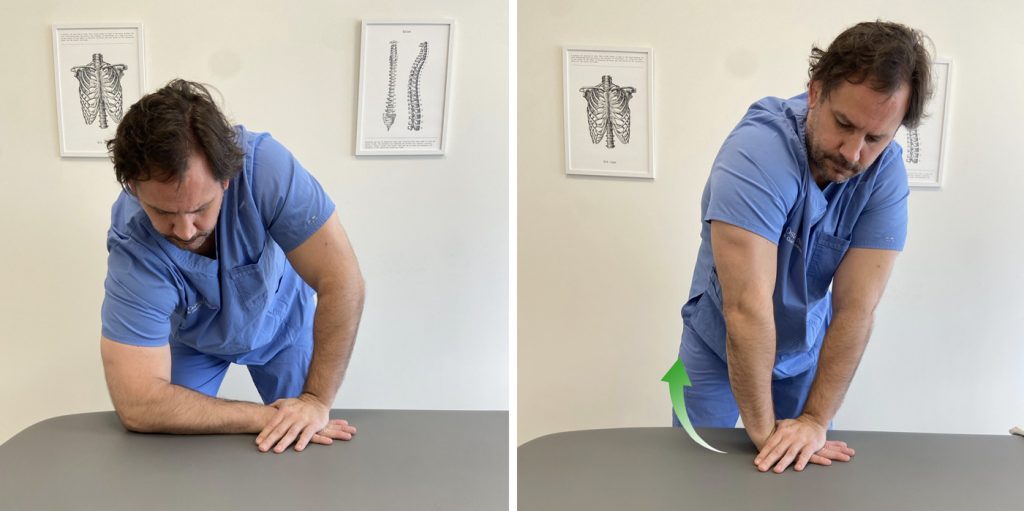

3. Estiramiento con la mano apoyada en una superficie plana y estable

Apoyamos la mano del lado que queremos estirar sobre una superficie plana y estable, como puede ser una mesa. La mano contraria se apoya sobre la mano a estirar, con un apoyo lo más cercano posible a la articulación de la muñeca, pero permitiendo el movimiento de esta.

Seguidamente elevamos el codo del lado a estirar hasta sentir el estiramiento en los músculos de la cara palmar del antebrazo.